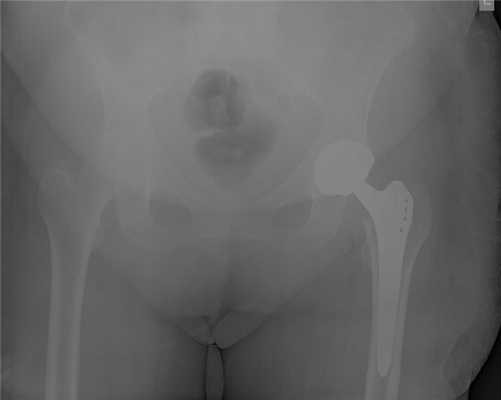

Рис.: Бесцементный тотальный эндопротез правого тазобедренного сустава, установленный в результате малоинвазивной операции по AMIS-технологии.

Бесцементный тотальный эндопротез правого тазобедренного сустава, установленный в результате малоинвазивной операции по AMIS-технологии.